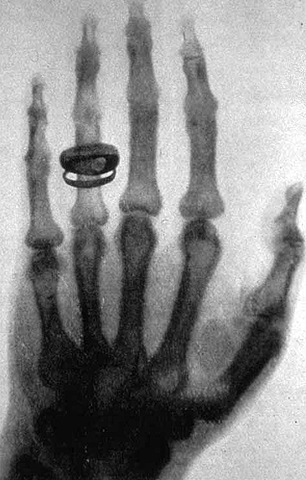

• Imagen de mano

Imagen de mano

Rontgen obtuvo la imagen de la mano de su esposa. Consiguió este resultado al poner una placa fotografía detrás de la pantalla.